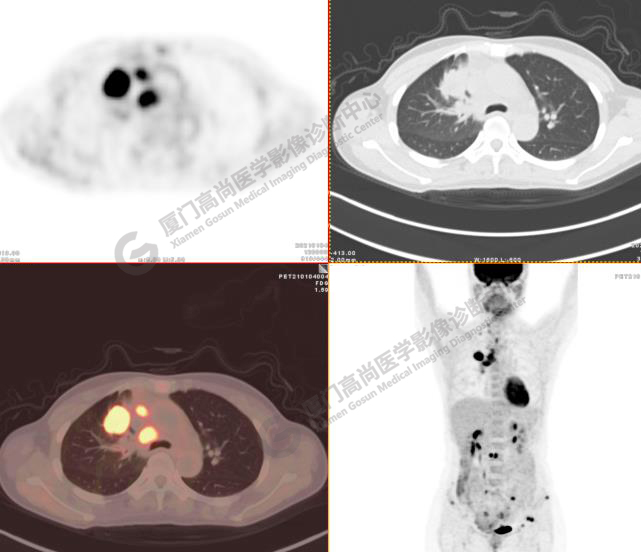

病例3:某女,47歲,咳嗽3周,無咯血,右上胸部疼痛,腰部疼痛

廈門市醫(yī)院查血腫瘤標(biāo)記物,CA153、CA724、CA211、NSE、AFP、CEA、CA125均正常

右肺上葉前段實(shí)性腫塊,大小約3.2x2.7x2.6cm,邊緣見毛刺、分葉,胸膜牽拉明顯,前段支氣管阻塞。FDG攝取增高,SUVmax,16.8;右側(cè)頸部Ⅳ區(qū)、右側(cè)鎖骨區(qū)、右肺門及縱隔淋巴結(jié)腫大, FDG攝取增高,SUVmax7.9;C2、L2椎體、右側(cè)第6肋骨、骶骨、髂骨、左側(cè)髖臼、腰椎體及附件骨質(zhì)破壞,SUVmax11.8。

影像診斷:右肺上葉周圍型肺癌并多發(fā)淋巴結(jié)、骨骼轉(zhuǎn)移。(TNM分期,T2aN3M1c Ⅳ B期)

病理診斷:低分化腺癌